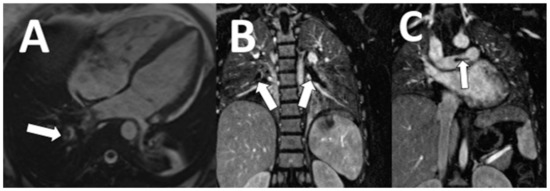

| Cholangiocarcinoma | 7 (28) |

| Hepatocellular carcinoma | 3 (12) |

| Aortic dissection | 2 (8) |

| Aortic aneurysm | 3 (12) |